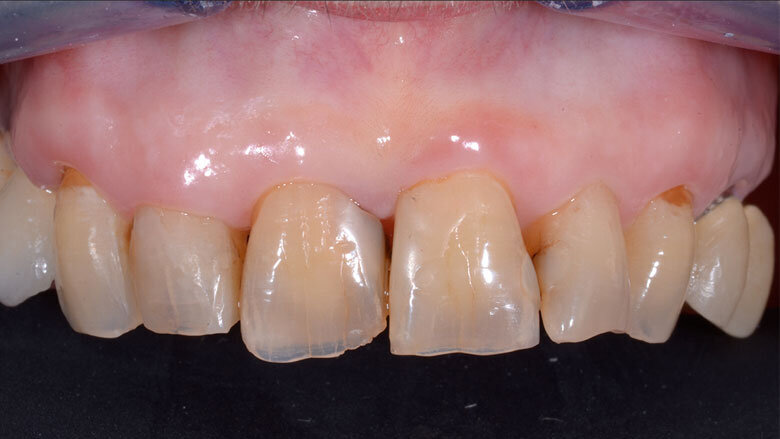

Un moncone in titanio per protesizzazione provvisoria (componente secondaria provvisoria - Straumann) viene modificato così da permettere un corretto alloggiamento della corona provvisoria e serrato manualmente. Protetto il canale della vite, il provvisorio viene forato in corrispondenza dell’accesso della vite protesica, posizionato in sede grazie alle alette e bloccato utilizzando del composito flow (G-aenial Universal flo - GC). Rimossa dal cavo orale, la corona provvisoria viene rifinita in laboratorio, completando il tragitto transmucoso in composito (Essentia Universal - GC) in modo tale da modellare un’area sotto-gengivale che sostenga i tessuti senza comprimerli. La riabilitazione provvisoria viene posizionata, avvitata e serrata a 20 N/cm. Il foro di accesso viene protetto con PTFE e sigillato con un’otturazione provvisoria (Telio CS onlay - Ivoclar), e i contatti occlusali vengono scaricati in modo tale da eliminare interferenze occlusali (Figg. 5, 6). Viene prescritta terapia farmacologica antibiotica, antidolorifica e sciacqui con collutorio a base di clorexidina digluconato. La paziente viene controllata a 7 giorni, 45 giorni e 90 giorni. A distanza di 3 mesi l’impianto viene considerato osteointegrato e i tessuti molli hanno raggiunto la loro stabilità. Il provvisorio viene quindi svitato (Fig. 7) e si procede tramite impronta ottica (Trios 3 - 3Shape) al trasferimento in laboratorio della posizione tridimensionale dell’impianto, della morfologia del tragitto transmucoso e della morfologia della componente sottogengivale della corona provvisoria (Figg. 8a, 9b). Una corona avvitata in zirconia con microstratificazione vestibolare viene confezionata come riabilitazione definitiva (Fig. 10). Superata la prova estetica, il manufatto viene consegnato e serrato a 35 N/cm. Il foro passante viene sigillato con PTFE e resina composita (G-aenial - GC) (Figg. 11, 12).

Fig. 11 - Valutazione post-operatoria: riabilitazione definitiva in situ in visione frontale.

Fig. 12 - Valutazione post-operatoria: riabilitazione definitiva in situ in visione occlusale.